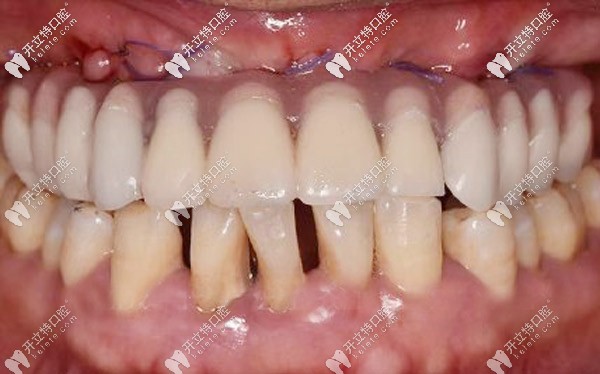

與周老先生進行溝通后,確定了種植體嵌入位置、數(shù)量、種植深度、植體傾斜角度等等,并采用上頜6顆即刻種植技術,運用“數(shù)字化動態(tài)導航種植”方案。

全程監(jiān)控種植位點、角度、深度,能夠避免損傷重要的解剖結構。這樣做可以節(jié)省大量的種植時間,縮短牙骨暴露在外的時間,保存了牙骨的活性,有利于植體和牙槽骨的緊密結合。